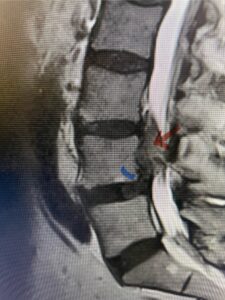

Fig. 3a : Sagittal T2-weighted lumbar MRI demonstrating a massive L4-5 disc herniation with superior migration behind the L4 vertebral body and taking up most of the left side of the spinal canal (red arrow) Note the slight grade one spondylothesis at L4-5 (blue dash). Notice the severe compression of the thecal sac (blue arrow) by the large left sided disc herniation (red arrow)